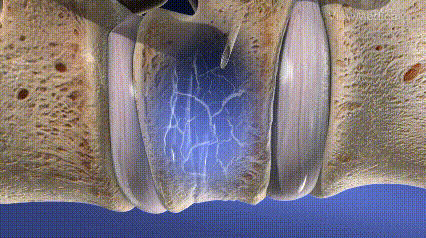

• 囊球扩张(仅PKP)

• 椎体恢复高度